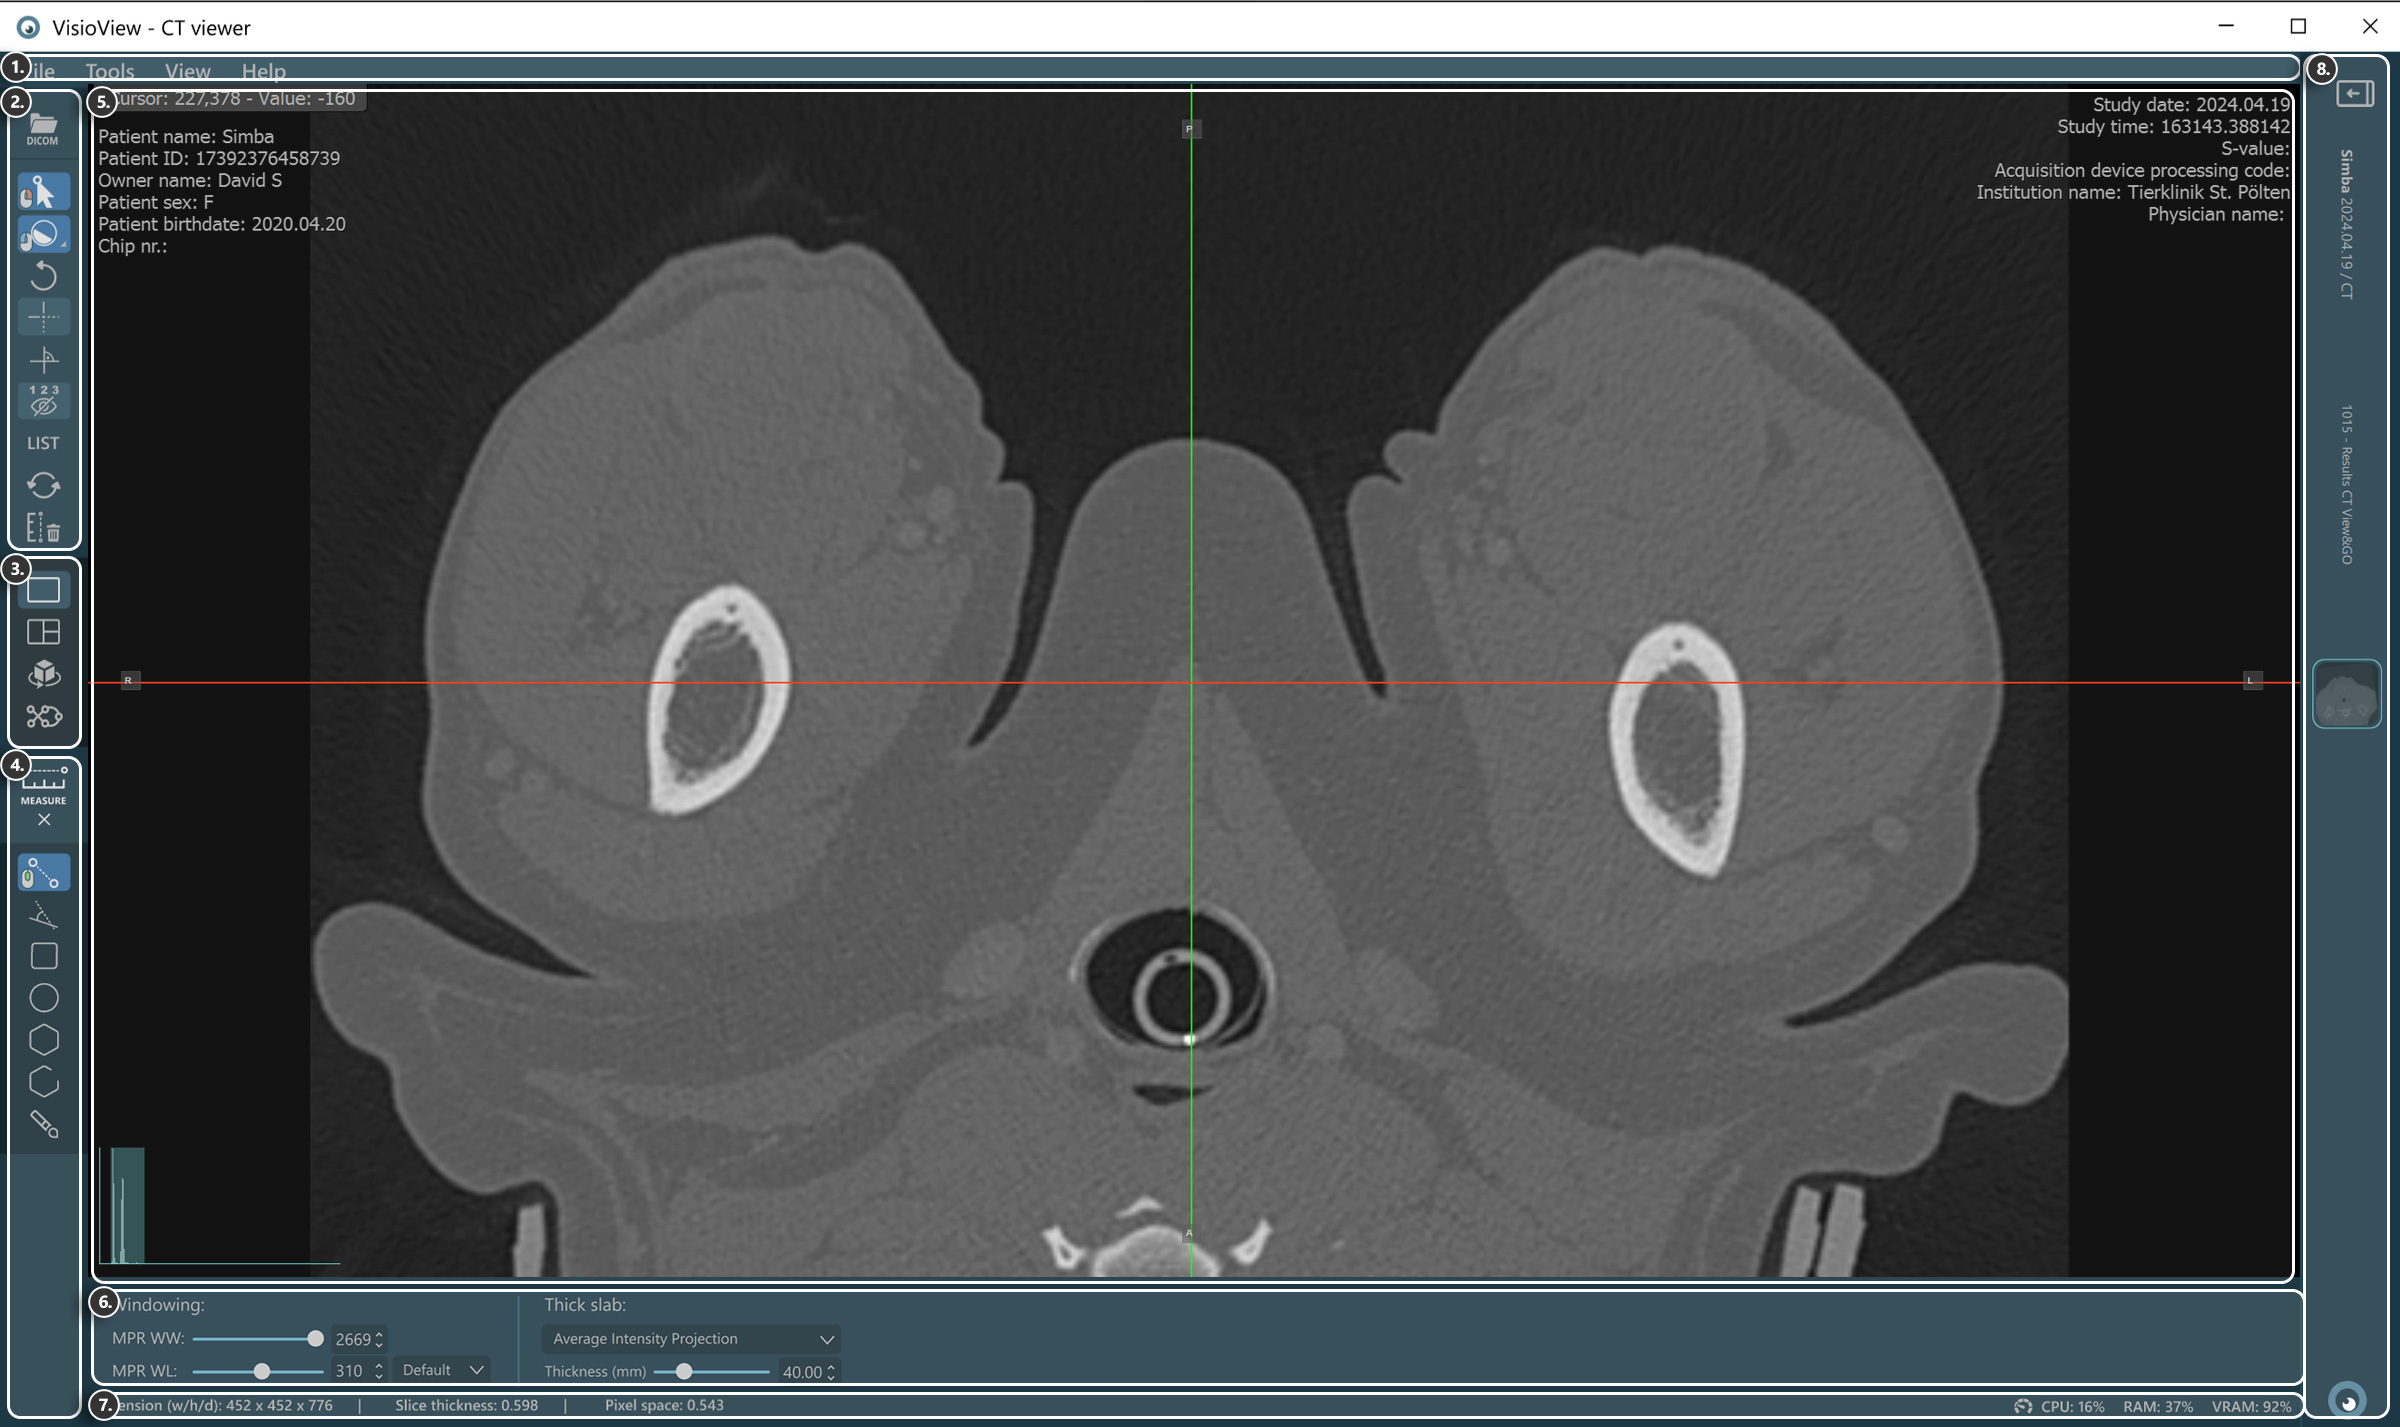

VisioVIEW - CT Viewer¶

The new VisioVIEW CT Viewer is a dedicated DICOM Viewer capable of 3D Multiplanar Reconstruction (MPR) of volumetric DICOM images (CT and MR modalities). Additionally, it also supports other viewing modes, including a 3D view offering simultaneous examination of all 3D planes (Axial, Coronal, and Sagittal) and 3D visualization of the body, a Curved MPR view (CMPR), Average Intensity Projection, Maximum Intensity Projection (MIP), and Minimum Intensity Projection (MinIP).

Sections of the VisioVIEW CT Viewer¶

The VisioVIEW CT Viewer consists of several sections, each tailored to a specific purpose. Below is a detailed description of each section.

View Selector¶

Measurement Tools¶

Viewer Area¶

View Settings and Options¶

Windowing settings

Thick slab settings

Information Bar¶

DICOM image and resolution information

Performance and resource usage information